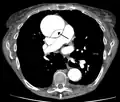

Stanford type B dissection of the descending part of the aorta (3), which starts from the left subclavian artery and extends to the abdominal aorta (4). The ascending aorta (1) and aortic arch (2) shown in the image are not involved in this condition.